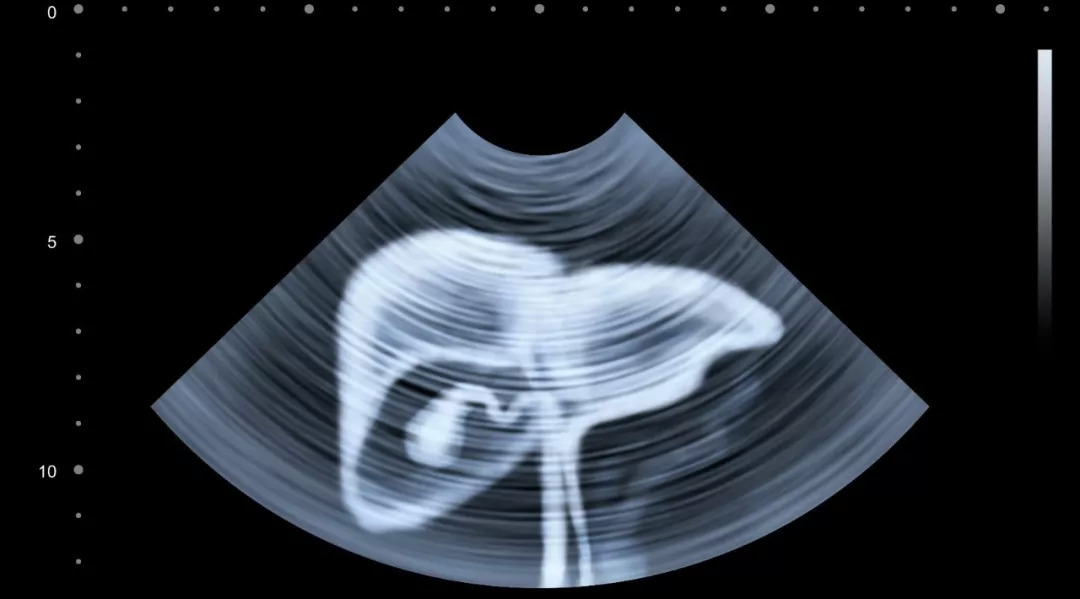

如果是前三类人(有乙肝、有肝硬化、家中有肝癌患者):建议每 6 个月做一次腹部 B 超检查 + 血清甲胎蛋白(AFP)检查;